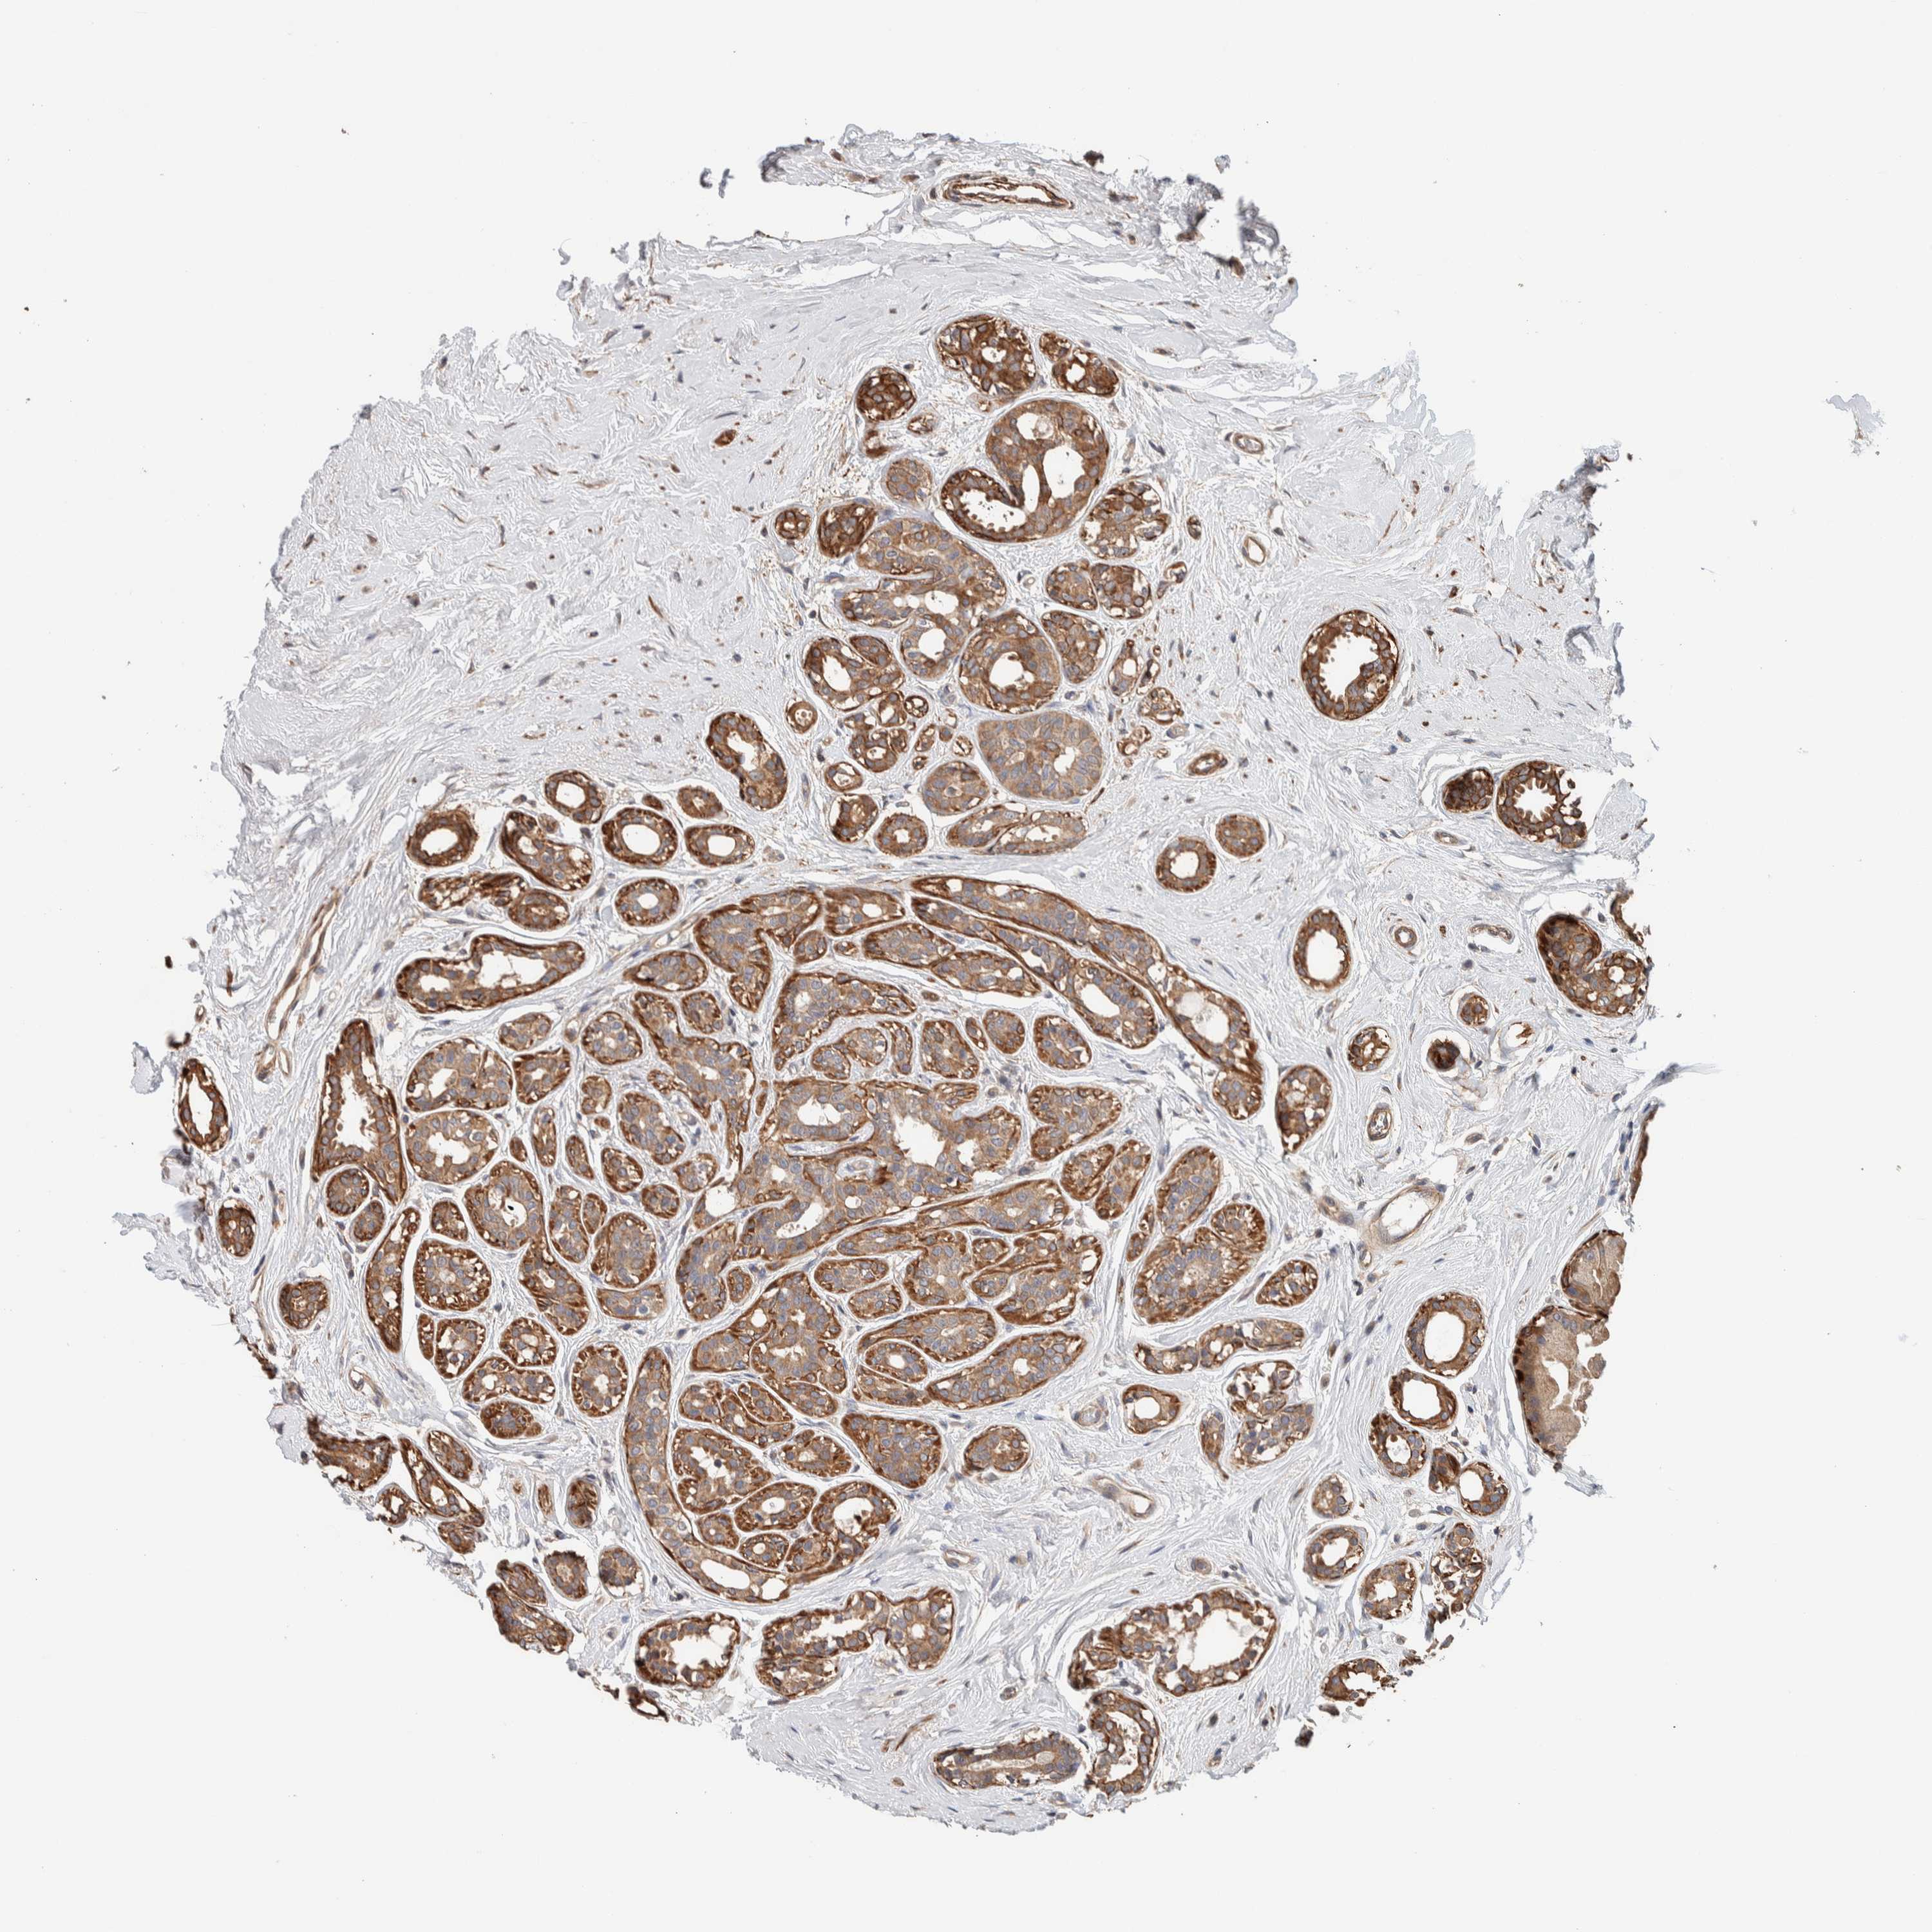

CANCER BREAST CANCER Show tissue menu

BRCA TCGA BRCA VALIDATION PROTEIN EXPRESSION